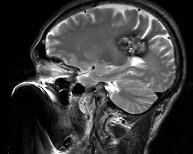

问题 男,59岁,反复头晕头痛半年余,重体力活时头痛明显,请根据所提供图像,选择最可能的诊断()

选项 A.(左顶)海绵状血管瘤 B.(左顶)室管膜瘤 C.(左侧脑室)胶质瘤 D.(左侧脑室)脉络膜乳头状瘤 E.(左顶)动静脉血管畸形

答案 A